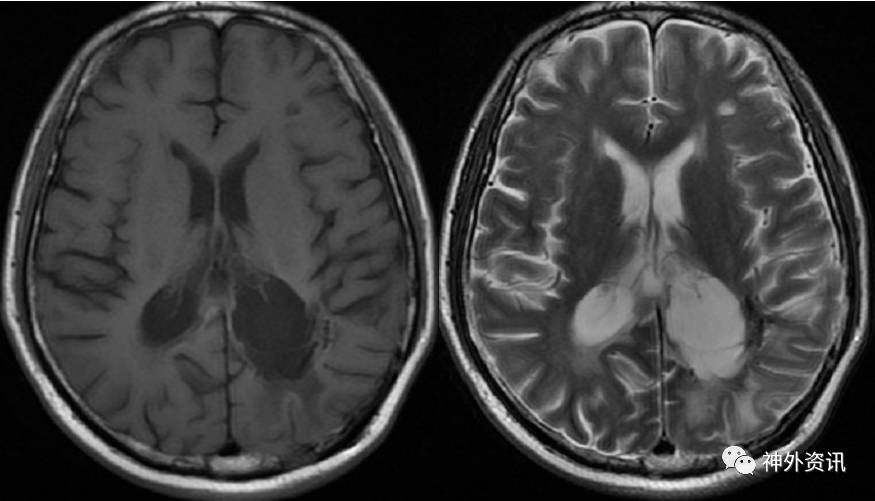

既往史:11年前(2005年)因“头痛1月”,行头颅MRI检查提示左顶枕肿瘤,胶质瘤?(图片未找到)收住我院,完善术前检查后行开颅肿瘤切除术。术后病理提示非霍奇金淋巴瘤,B细胞性,部分细胞核较大,考虑大B细胞型。术后放疗18次(全脑6MV-X线DT3600 Cgy/18F,面积12*16.5cm2);化疗1次(具体方案不详),因患者不耐受化疗而停药。术后多次复查头颅MRI增强,未见肿瘤复发,于2009.4.16最后一次复查头颅MRI增强,未见肿瘤复发(图2)。之后患者未再复查头颅MRI。

图2. 术后4年复查MRI,增强扫描未见肿瘤复发